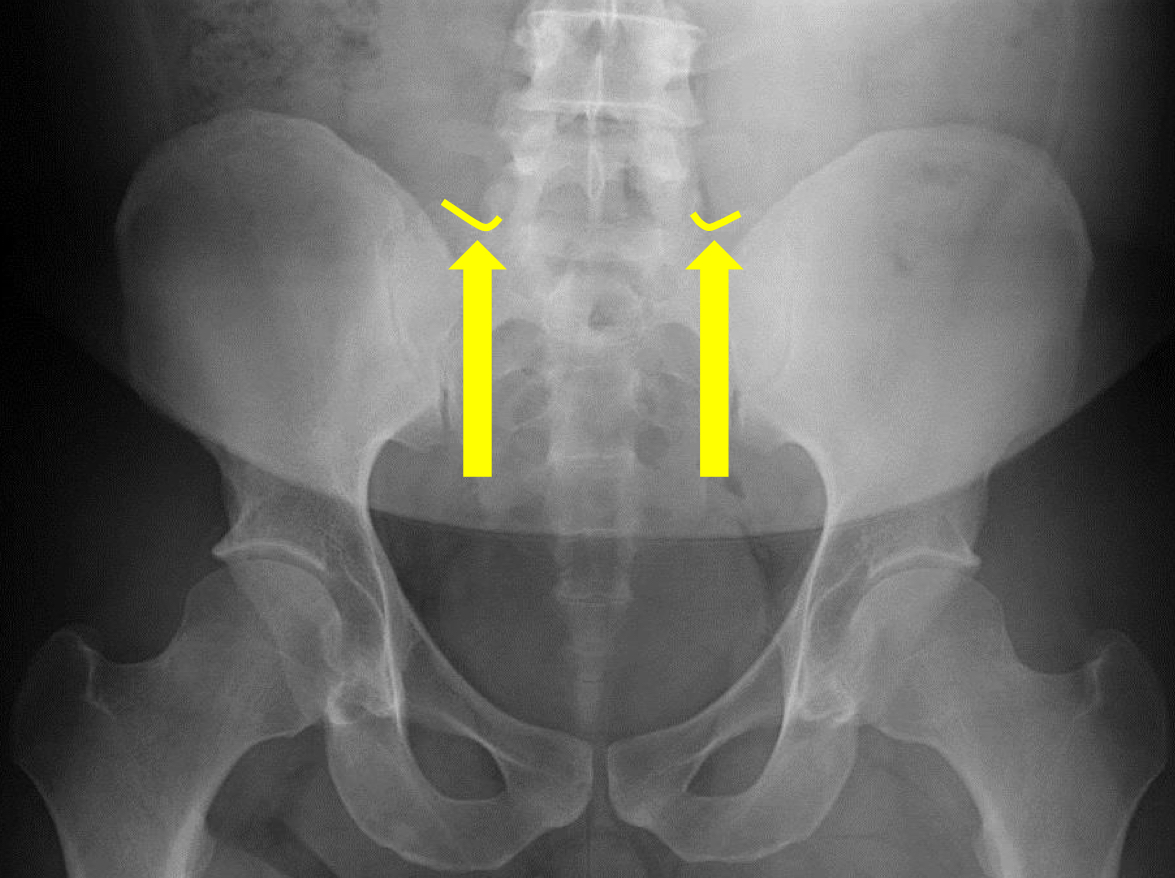

What view is this?

AP (Anterior to Posterior) LumboPelvic

What is this?

Femur Heads

What is this?

Superior Iliac Crests

What is this?

Lateral Iliac Crests

What is this?

Ischial Tuberosites

What is this?

Obturator Foramen

What is this?

S2 Tubercle

What is this?

Pubic Symphysis

What is this?

Sacral Groove

What is this?

Lateral aspect of sacrum

What is this?

Medial Aspect of Ilium